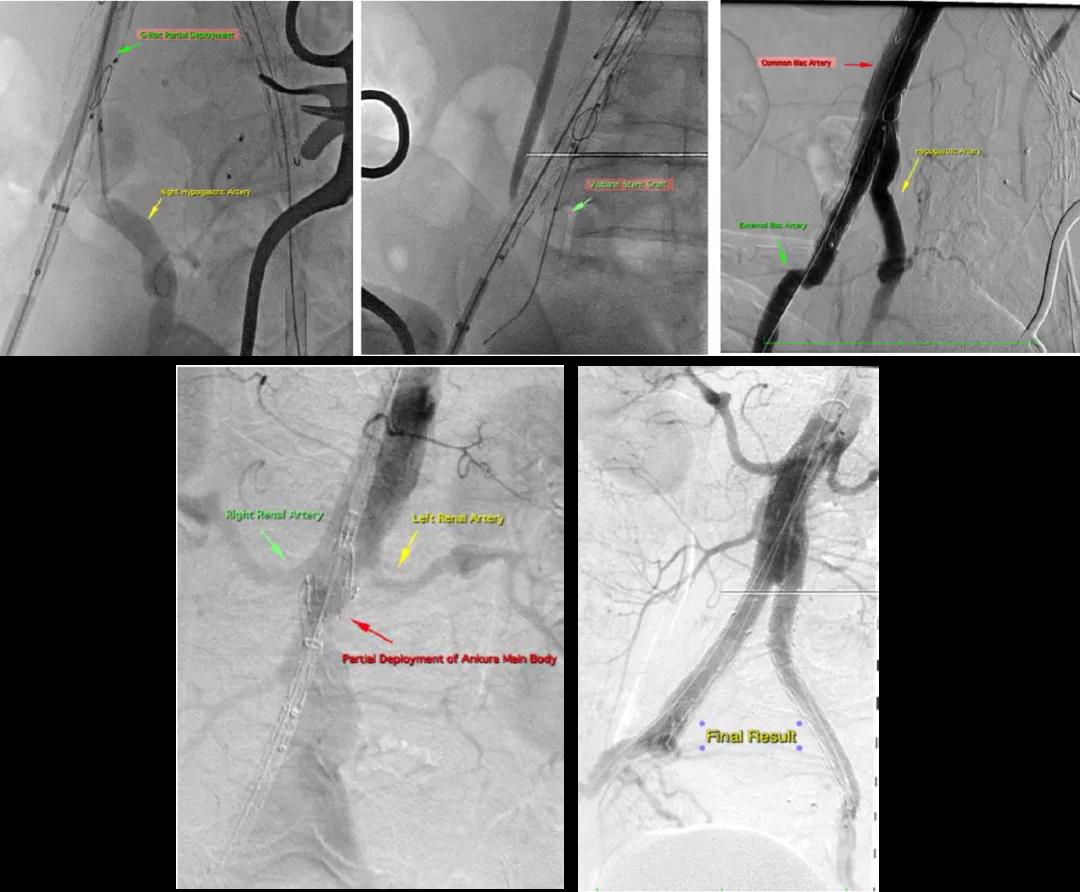

手术在委内瑞拉Ascardio医院顺利进行,Prof. Jesús Garcia首先从左侧入路,通过Fustar™可调弯鞘将Cera™血管塞输送到患者左侧髂内动脉,对左侧髂内动脉进行栓塞,然后再从右侧入路,植入Ankura™腹主动脉覆膜支架隔绝腹主动脉瘤,随后送入G-iliac™髂动脉分叉支架系统完成重建患者右侧髂内动脉。每一个环节都有条不紊的进行,术后造影显示支架位置形态良好,瘤体隔绝完全,支架内血流通畅,且无内漏及任何并发症发生,患者在术后3天便顺利出院。

(Prof. Jesus Garcia团队使用彩神在线网信彩票-彩神通免费版下载-彩神8争霸vlll-彩神购彩购彩大厅-彩神软件陆立根免费版-彩神ll争霸3-彩神ll彩神8-彩神ll争霸彩票-拼搏在线彩神网网页版系列创新产品为患者进行手术)

(术中、术后造影)